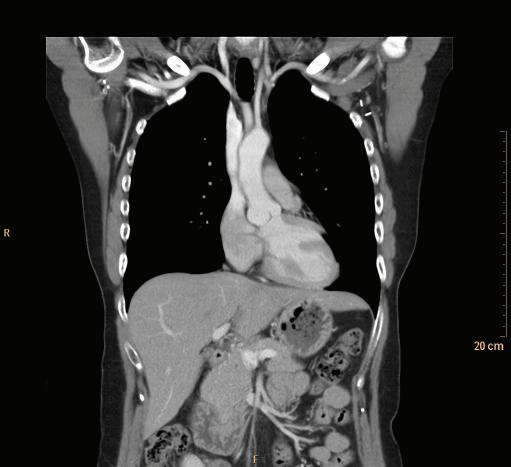

FIGURE 1-18 Coronal CT of the chest.